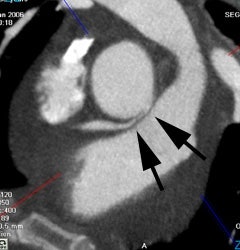

Coronary artery calcification: The patient below has a large calcification in their proximal LAD. Their total calcium score was 537. |

|